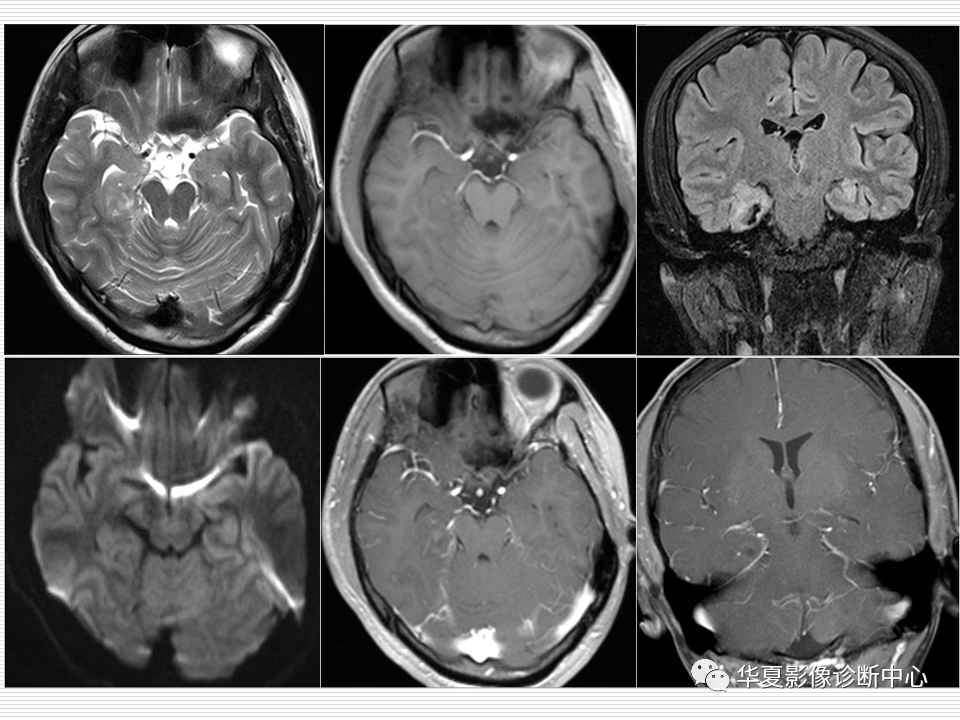

海马正常解剖与疾病影像诊断

图片尺寸1280x720